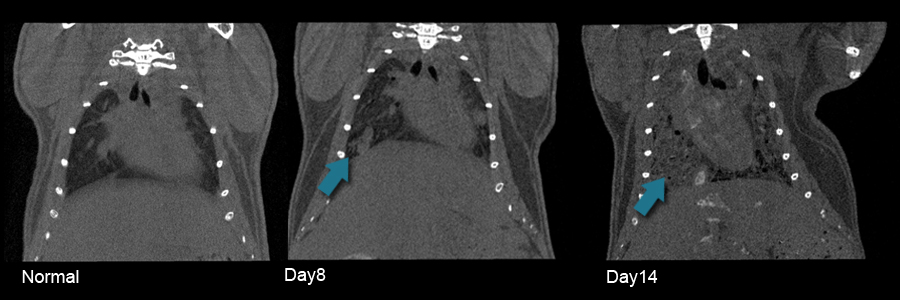

妊娠を契機に出現した悪性黒色腫の1例 drmtl. 妊娠を契機に出現した悪性黒色腫の1例 かったが一部にメラノーマ様細胞を認めたため これまで妊娠中に生じたmmに. メラノーマ??進行してる??|女性の健康 「ジネコ」. メラノーマは確かに怖い病気ではあると思いますが、10万人に1人か2人の頻度の少ない病気ということです。また、メラノーマについてはここで聞くよりも大学病院の皮膚科のホームページなどが参考になりますよ。. Causas del cáncer de lengua factores de riesgo del cancer. Also try. Cáncer de lengua causas, primeros síntomas y tratamiento. Los tumores de lengua más pequeños con menos de 4 cm, pueden ser tratados bien con cirugía o con radioterapia. En estos casos el 80% de los pacientes se suelen recuperar satisfactoriamente. メラノーマの原因、症状、治療. 妊娠中のメラノーマは経過が悪くなることは以前から知られています。 この他、カフェインの総摂取量が多いとメラノーマの発症リスクが減るという調査結果、柑橘類の摂取が多いとメラノーマの発症リスクが上昇するという調査結果などもあります。.